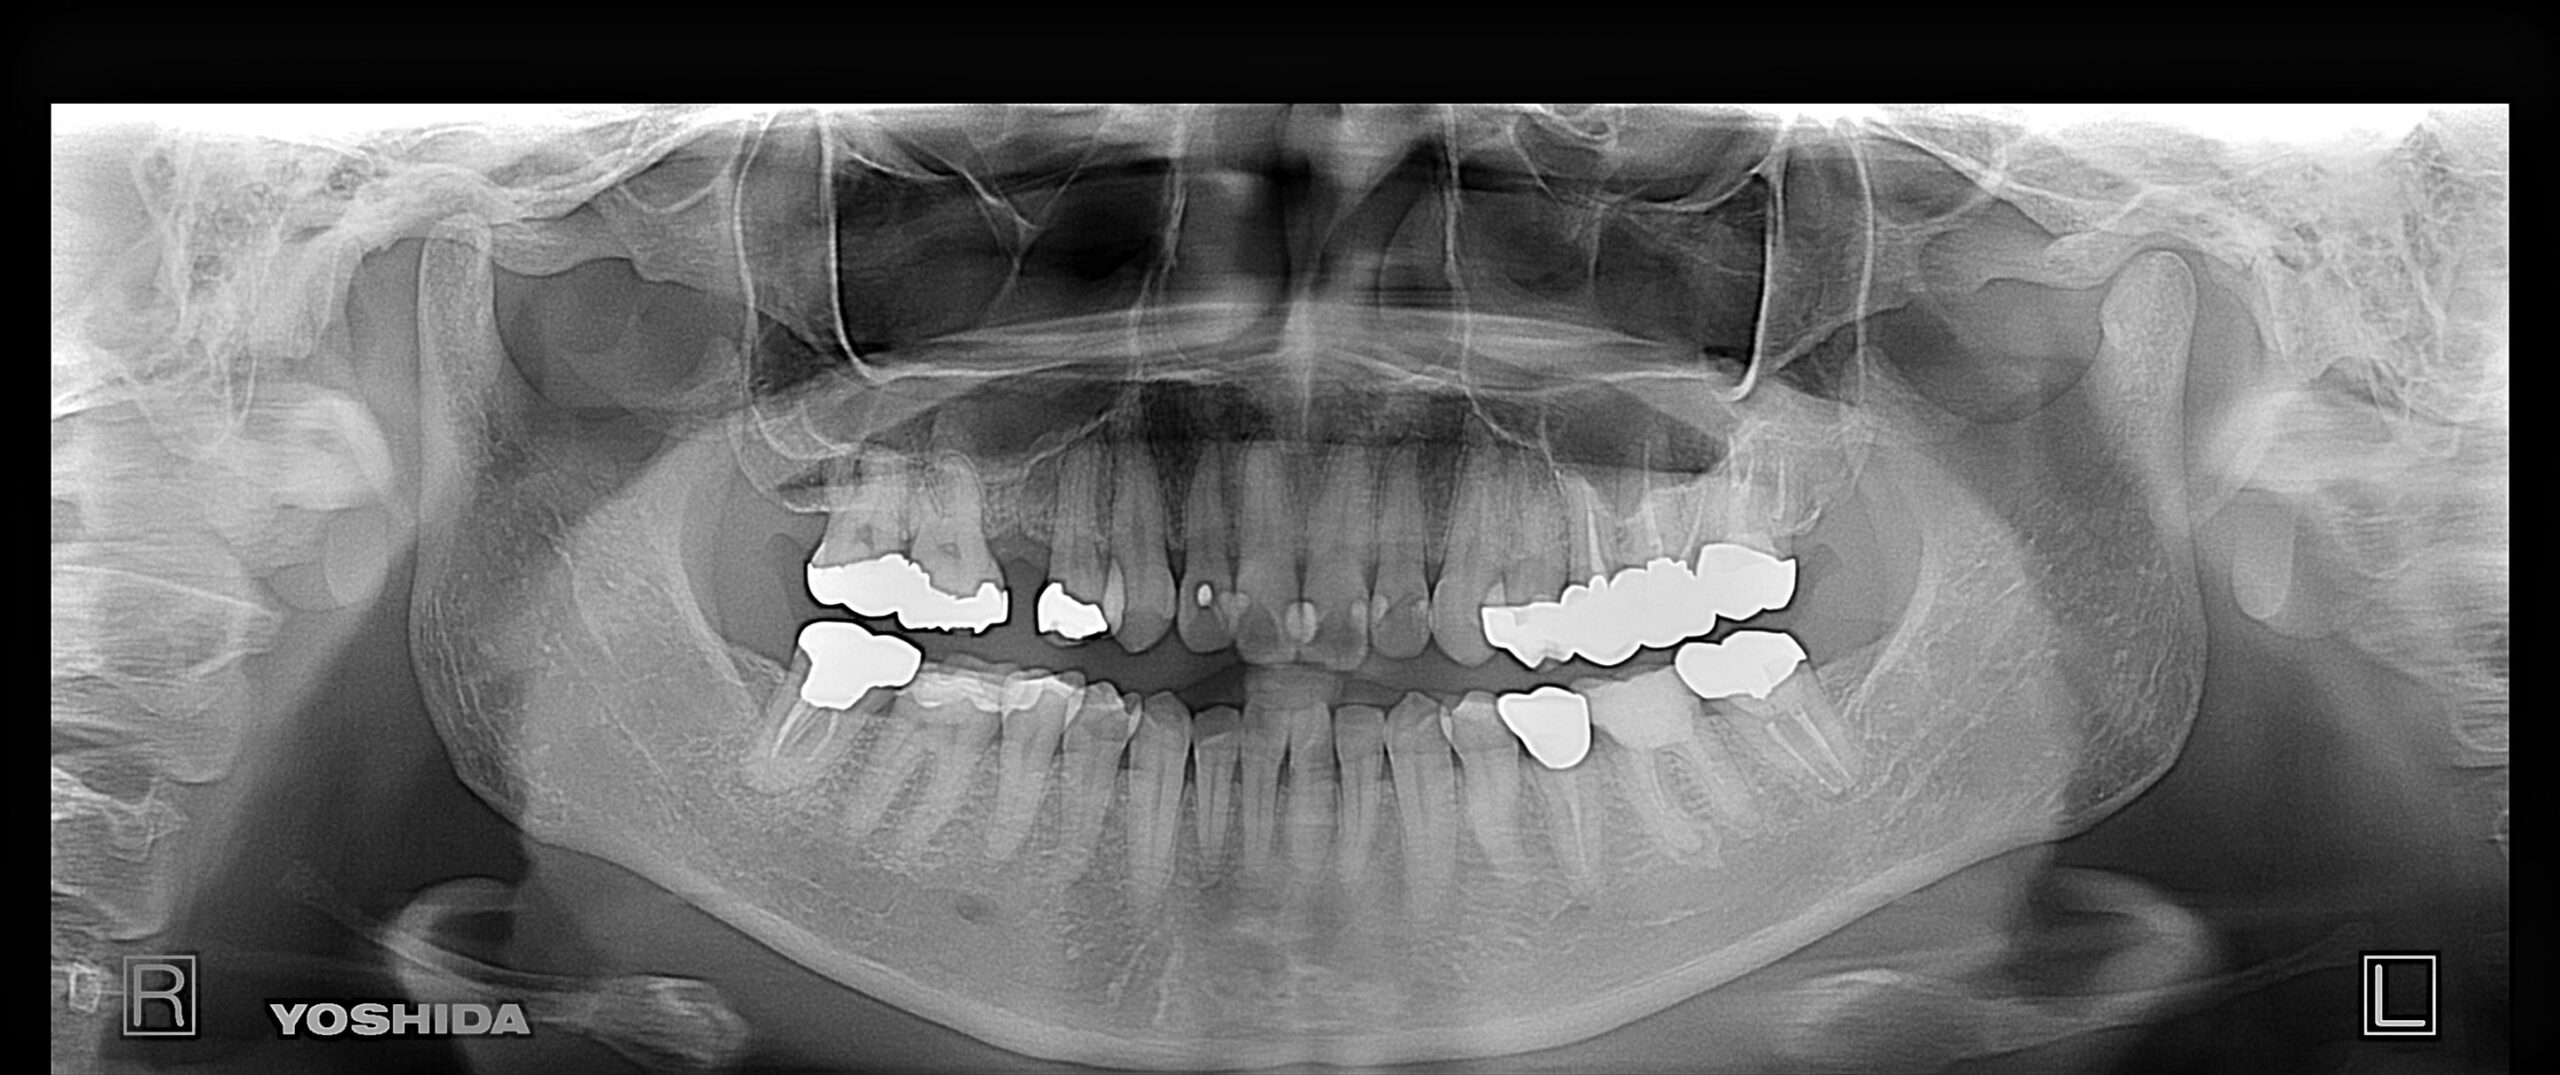

右下奥歯のインプラント症例

Before

• 右下6番欠損です。

• インプラントを埋入するのと同時にヒーリングキャップを取り付けました。

After

治療内容

右下の奥歯を根の先の膿が原因で抜歯された患者様です。

ブリッジ治療では両隣の歯を大きく削らないといけない為、インプラント治療を希望されました。

骨の治り方が歪で、頬側の骨が大きく足りないため骨造成を行い、インプラントを埋入した日にヒーリングキャップを装着し、インプラントが骨と結合するまで待ちます。

その後、型取りをし被せ物をスクリューにて装着しています。

担当歯科医師:平沼 佳朗

治療期間・回数

約10か月

費用

骨造成込み ¥616,000

リスク・副作用

術後に痛みや腫れ、出血を伴います。

口腔内の清掃不良によりインプラントの歯周病(インプラント周囲炎)になる可能性があります。定期的なメインテナンスが必要です。